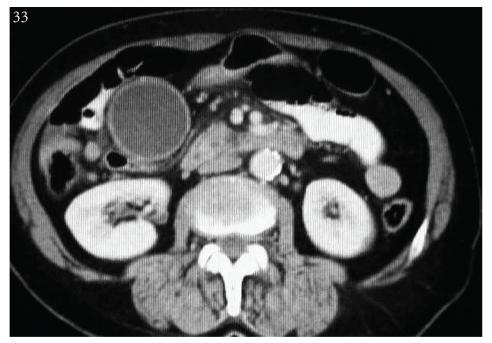

Introduction. Carcinoid tumors are low-grade tumors originating from endoderm and mostly involving the gastrointestinal system. However; they may be seen in any site within the gastrointestinal system. Case Presentation. A 69-year-old female patient. The results of blood tests were observed to be consistent with obstructive jaundice. A mass appearance was not encountered on tomographic examination. Papilla that was tumor-like macroscopically was seen in the second part of the duodenum in diagnostic endoscopy. Pylorus-preserving pancreaticoduodenectomy surgical procedure was applied. On pathological examination of the mass, a tumoral mass was detected in ampulla vateri localization, 1.5 × 1 × 0.8 cm in size, which, in immunohistochemical staining, was evaluated as a neuroendocrine tumor. Also, Metastasis was observed. Conclusion. The rarest type of carcinoid tumor is ampullary located carcinoid tumor, and tumor size is not a reliable indicator for tumor aggressivity in ampullary carcinoid tumors.

引言。类癌肿瘤是起源于内胚层的低度肿瘤,主要累及胃肠道系统。然而,它们可见于胃肠道系统内的任何部位。病例报告。一名69岁女性患者。血液检查结果显示与梗阻性黄疸相符。断层扫描检查未发现肿块表现。诊断性内镜检查时,在十二指肠第二部可见肉眼呈肿瘤样的乳头。实施了保留幽门的胰十二指肠切除术。对肿块进行病理检查时,在 Vater壶腹部位检测到一个肿瘤性肿块,大小为1.5×1×0.8厘米,免疫组化染色评估为神经内分泌肿瘤。此外,观察到有转移。结论。壶腹类癌肿瘤是类癌肿瘤中最罕见的类型,肿瘤大小不是壶腹类癌肿瘤侵袭性的可靠指标。